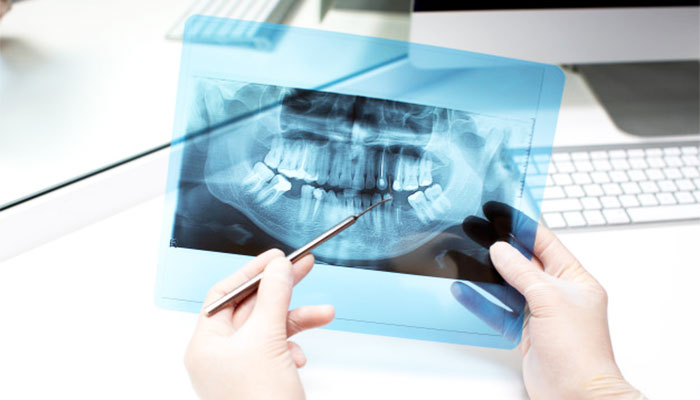

یکی از برجسته ترین پیشرفت ها در زمینه دندانپزشکی و کمک به تشخیص دقیق تر، رادیوگرافی دندان بوده است. این تکنیکهای تصویربرداری به ابزارهای حیاتی برای دندانپزشکان تبدیل شدهاند و بینشهای مهمی را در مورد سلامت دندان ارائه میدهند که با چشم انسان قابل رؤیت نیستند. در این مقاله به بررسی رادیوگرافی دندان میپردازیم.

رادیوگرافی دندان یک فناوری تشخیصی است که از تصویربرداری اشعه ایکس برای به دست آوردن تصاویر دقیق از بافتهای دهان استفاده میکند و به دندانپزشکان اجازه میدهد مناطقی را که در معاینات فیزیکی دیده نمیشوند و نیاز به بررسی از طریق اشعه ایکس دارند را مشاهده کنند. این امر به شناسایی زودهنگام، برنامه ریزی دقیق درمانی و مراقبت های کلی سلامت دندان کمک می کند. رادیوگرافی دندان به دلیل ماهیت غیر تهاجمی آن، در دندانپزشکی مدرن بسیار رایج و دارای اهمیت است.

اشعه ایکس دندان، نمای دقیقی از ساختار دندان و استخوان ارائه می دهد و ارزیابی جامعی از کل حفره دهان ارائه می دهد. این کار به دندانپزشکان اجازه می دهد تا سلامت ریشه دندان، استخوان فک و بافت های اطراف را ارزیابی کنند. در ارزیابی رشد دندان در کودکان، شناسایی ناهنجاری ها و برنامه ریزی درمان های ارتودنسی ارزشمند است.